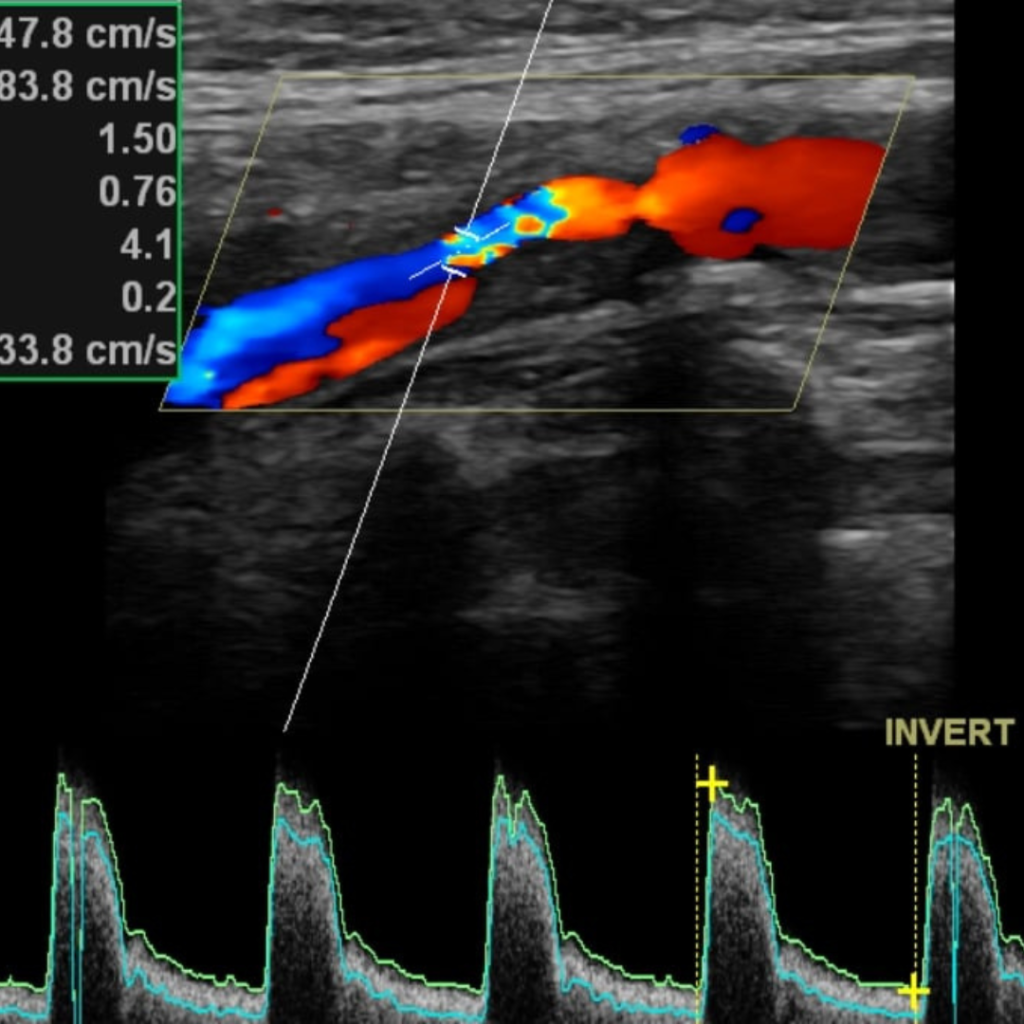

Уромед эмнэлгийн мэдрэлийн кабинет нь БНСУ-ын 2025 онд үйлдвэрлэсэн орчин үеийн шилдэг Samsung Medison V6 загварын хиймэл оюун ухаан дээр суурилсан аппаратаар тархины судасны өнгөт хэт авиан Допплер-Дуплекс шинжилгээг хийдэг.

тархины судасны өнгөт хэт авиан Допплер-Дуплекс шинжилгээгээр

Тархины судасны цусны урсгалын хурд, хөдлөл зүй

Судасны ханын

бүтэц, хатуурал, товруу

Гавлын гаднах,

доторх судасны

нарийсал, бөглөрлийг

Хиймэл оюун ухаан дээр суурилсан автомат хэмжилтээр маш өндөр түвшинд нарийвчлан дүрслэн харж үүссэн судасны атеросклерозын товруу, эмгэгийг хэмжиж, судасны нарийслын хувийг тогтоож, бөглөрөл буй эсэхийг шууд харж оношлогоо хийдгээрээ маш давуу талтай.

Тархины судасны өнгөт хэт авиан дуплекссонографи шинжилгээ нь тархины судасны өвчнүүд, тархины цус хомсрох харвалт, шигдээс үүсэхээс урьдчилан сэргийлэх, эрт илрүүлэх, оношлоход чухал ач холбогдолтой дүрс оношилгооны бусад аргуудтай харьцуулахад харьцангуй өртөг багатай, цаг хугацаа хэмнэсэн инвазив бус шинжилгээний арга юм.